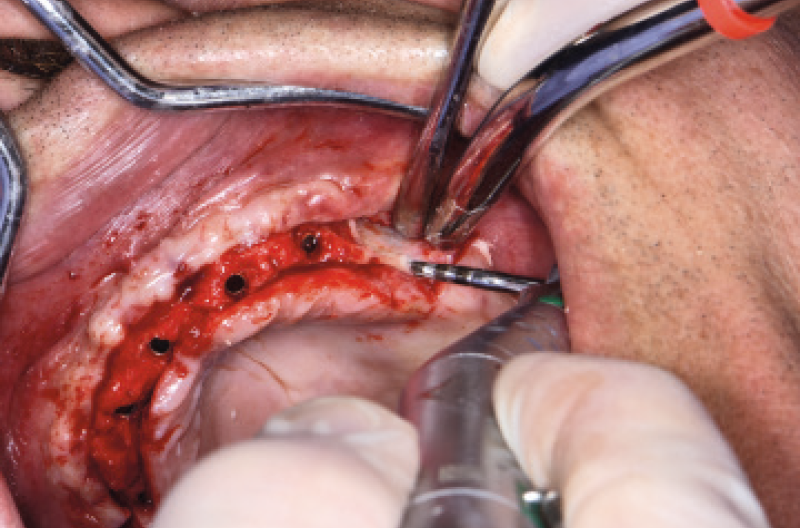

Nel mese di luglio 2019 il paziente ├© stato operato con il contestuale inserimento di 10 impianti, 4 nellŌĆÖarcata inferiore e 6 nellŌĆÖarcata superiore. Ho inserito 4 impianti Max Stability ├ś 3,75 mm nella zona della premaxilla, uno lungo 10 mm e gli altri tre da 12 mm di lunghezza; in regione 15 e 25 ho dovuto invece utilizzare delle frese da osseodensificazione per compattare lŌĆÖosso e traslare la parete mediale del seno mascellare per poter inserire 2 impianti Max Stability ├ś 3,75 L 12 mm inclinandoli lungo la parete stessa. Data la scarsa quantit├Ā e qualit├Ā di osso nel mascellare, ho rinunciato al carico immediato rinviando la procedura della protesizzazione immediata nella fase di riapertura degli impianti ad osteointegrazione avvenuta (Figg. 1-14).

Fig. 12 – Posizionamento dei tappi di chiusura

Fig. 13 – Innesto di osso autologo

Fig. 14 – Sutura